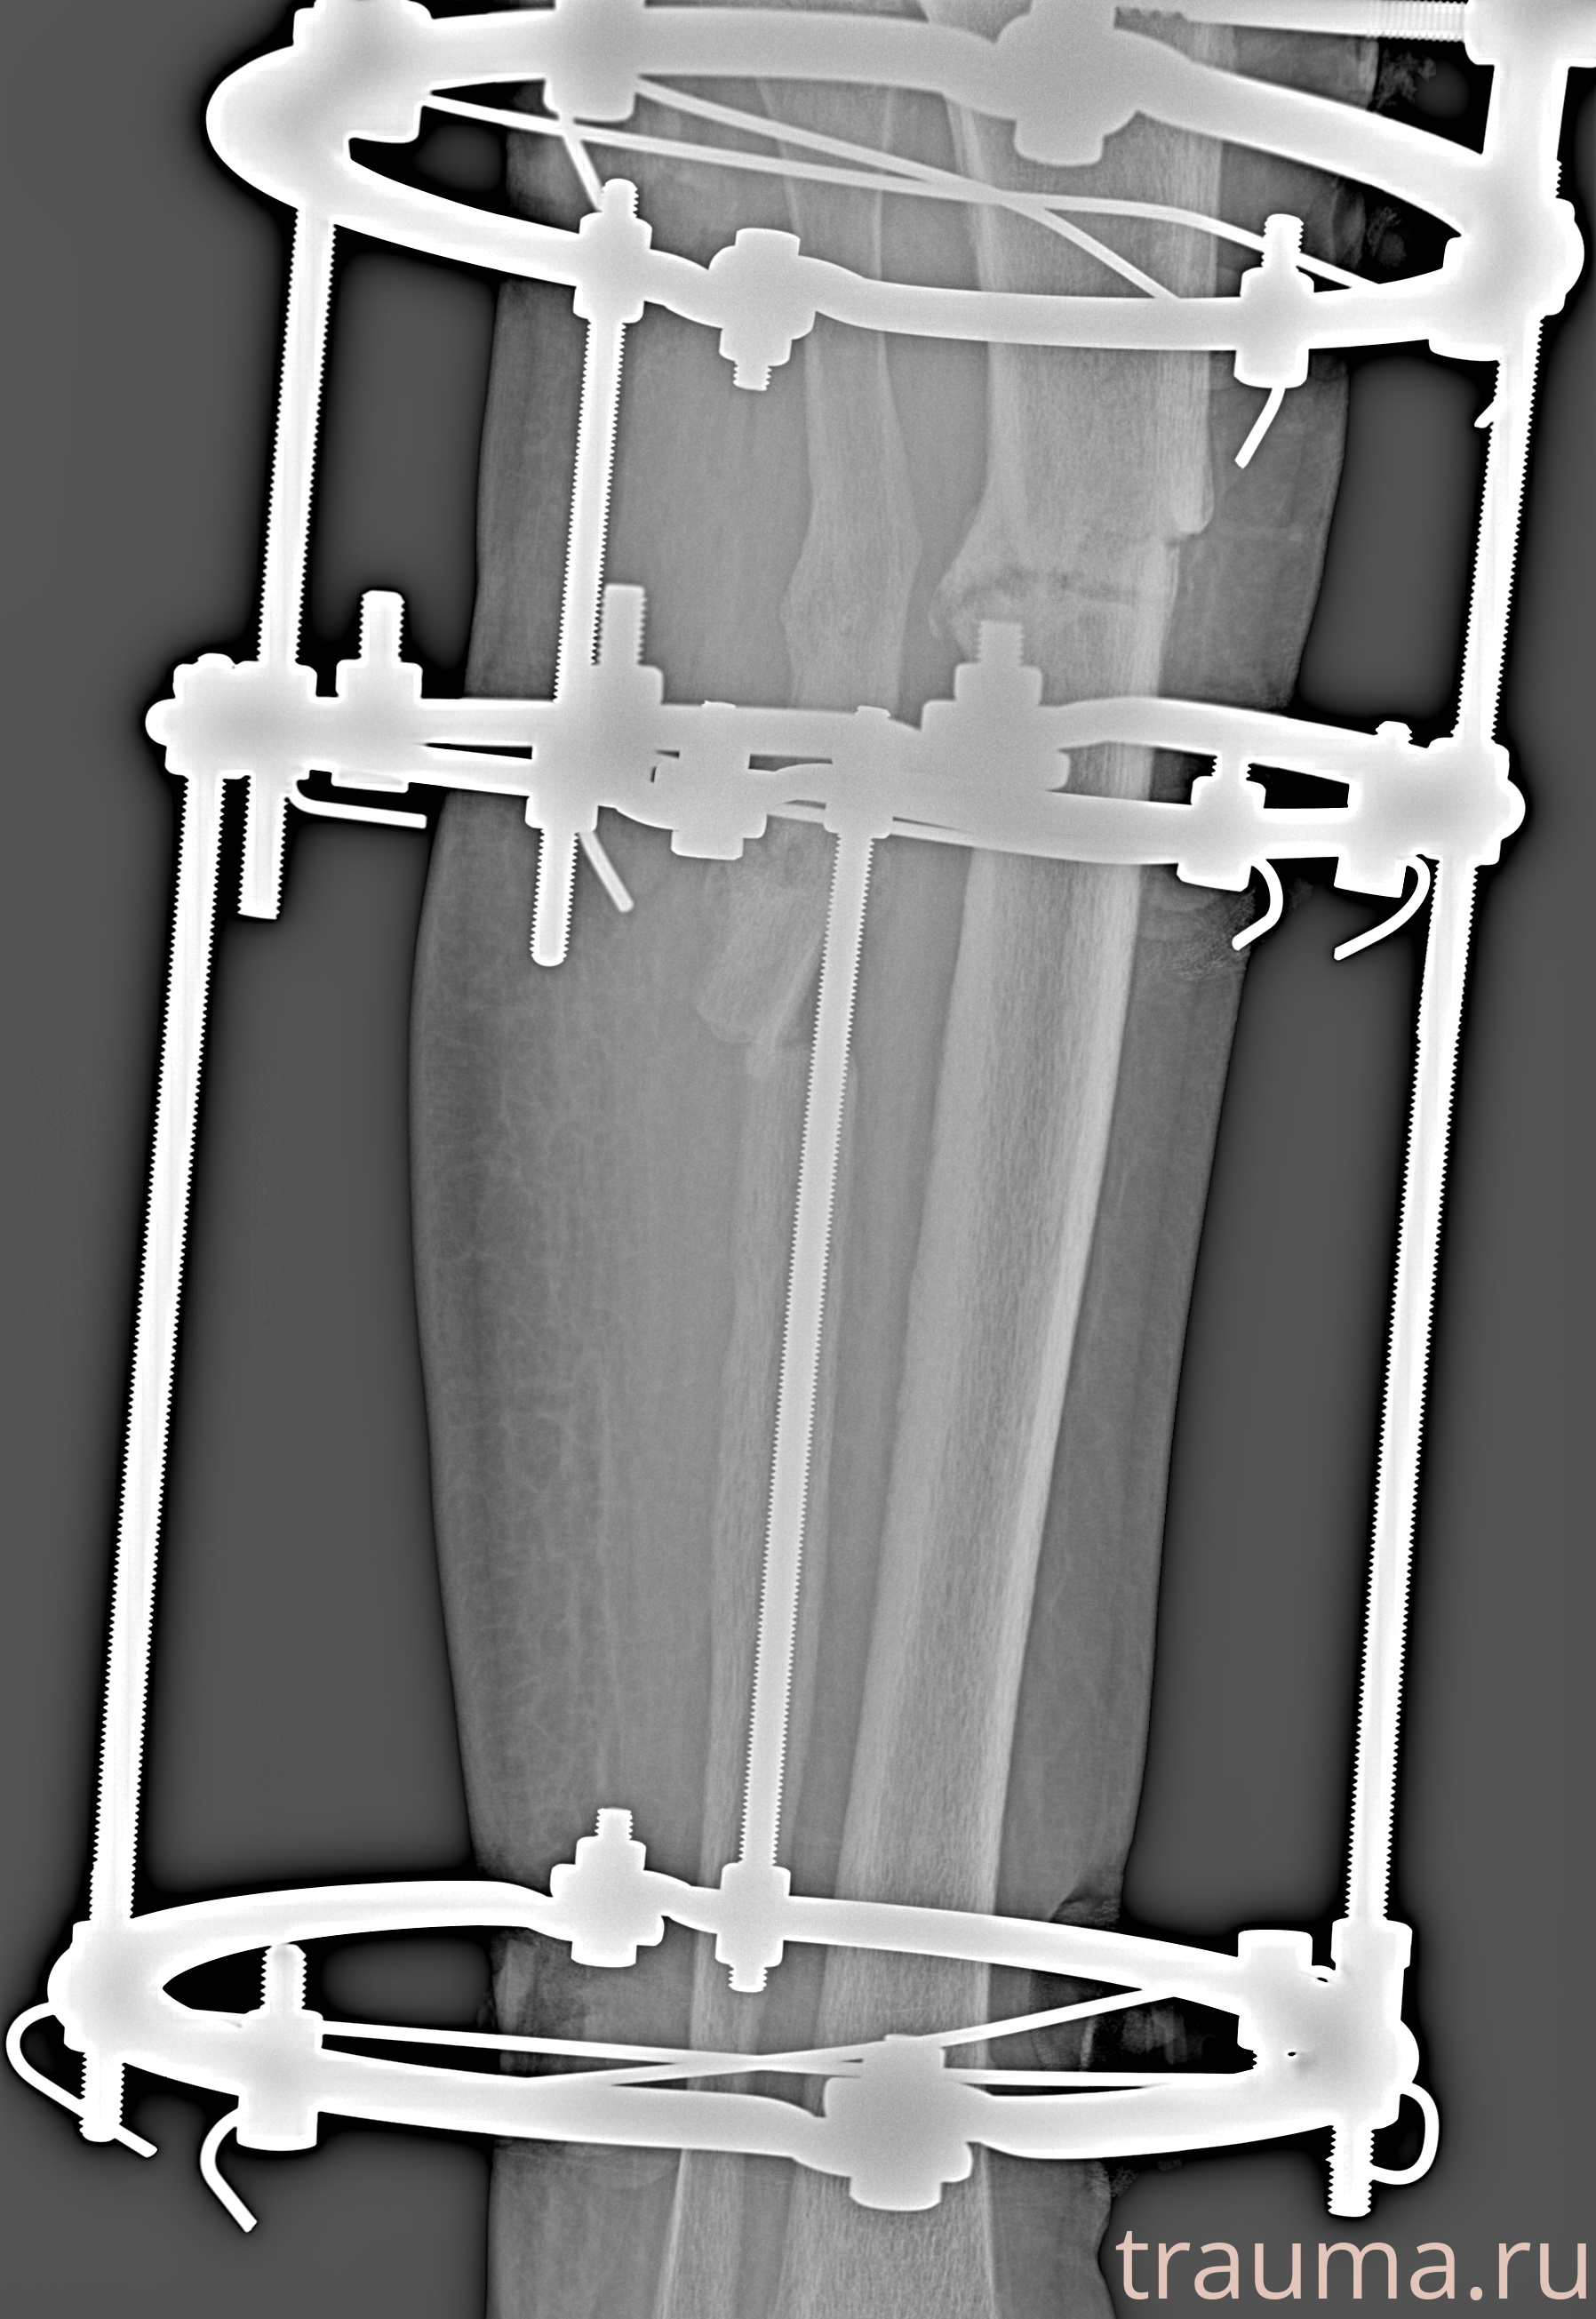

Рентгенограммы